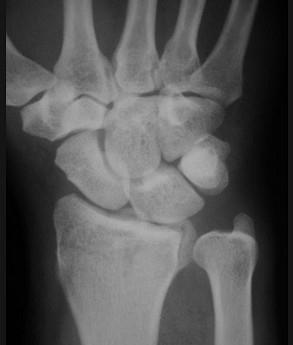

问题 男,22岁,滑冰时摔倒右手撑地时受伤,请结合CR片,选出最可能的诊断 ( )

选项 A、桡骨远端骨折 B、反柯莱斯骨折 C、蒙泰贾骨折 D、加莱阿齐骨折 E、柯莱斯骨折

答案 A